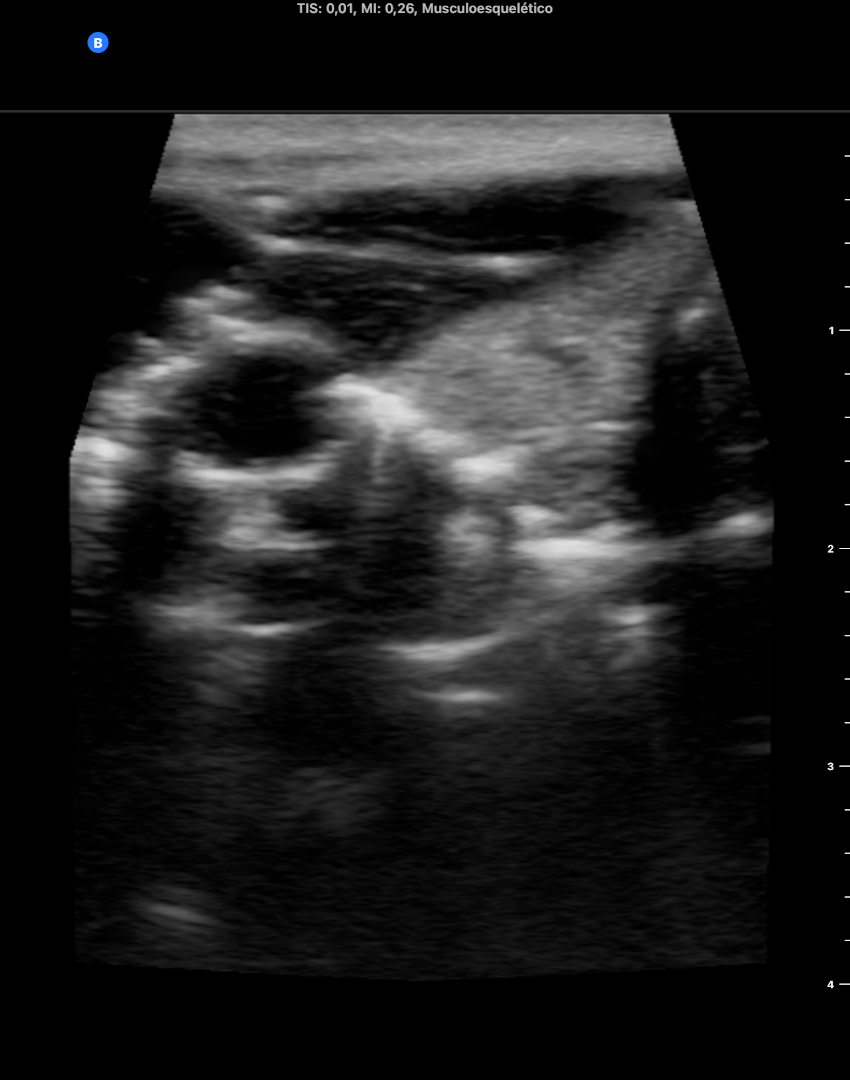

Ecoscopia: líneas A artefactuales a nivel de zona cervical izda. que borra la anatomina del tiroides y vasos cervicales. Anatomía cervical derecha normal. Ventana pulmonar sin neumotórax en modo M. Ventana cardíaca en eje paraesternal corto borrado por líneas A que no permiten valoracion correcta. Abdomen sin líquido libre ni líneas A.

Ecoscopia tras 1 semana del diagnóstico ecoscópico normal a todos los niveles anatomicos (cervical, pulmonar, cardíaco, abdominal).